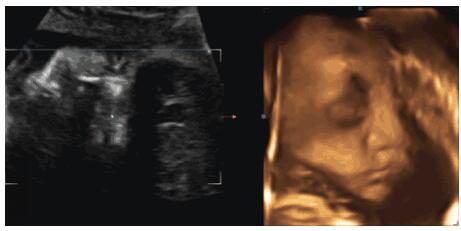

事实上,胎儿确实会在子宫内哭,而且已有不少的孕妇证实有时候会听到肚子里的宝宝哭。除此之外,据英国《卫报》报道,科学家首次使用4D超声波成像系统时发现,婴儿在出生前数周就已经会大哭不已了。

四维彩超是筛查胎儿畸形的重要手段。在这里,小编想要提醒准妈妈一句,四维彩超您预约了吗?如果还没有的话,请尽早预约哟!金猴宝宝+全面二胎,城阳玛丽妇儿医院四维彩超室外,每天轮流做四维的准妈妈都很多。